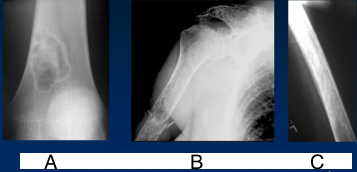

What disease is this? What is shown by A, B and C? | Psoriatic arthritis. A = destructive changes B = Pencil in cup deformity C = IPJ fusion |